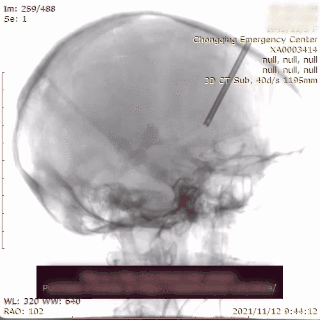

送入3.0mm*15mmNeuroform Atlas支架并释放,头端位于P3段,尾端位于P2段,释放后Atlas支架的Mark点显影良好。观察10分钟,P2段及远端血流仍通畅,未见血栓形成,遂结束手术。

术后即刻影像

治疗后工作位减影造影显示动脉瘤栓塞满意,载瘤动脉血流通畅。

术后CT提示支架打开良好。